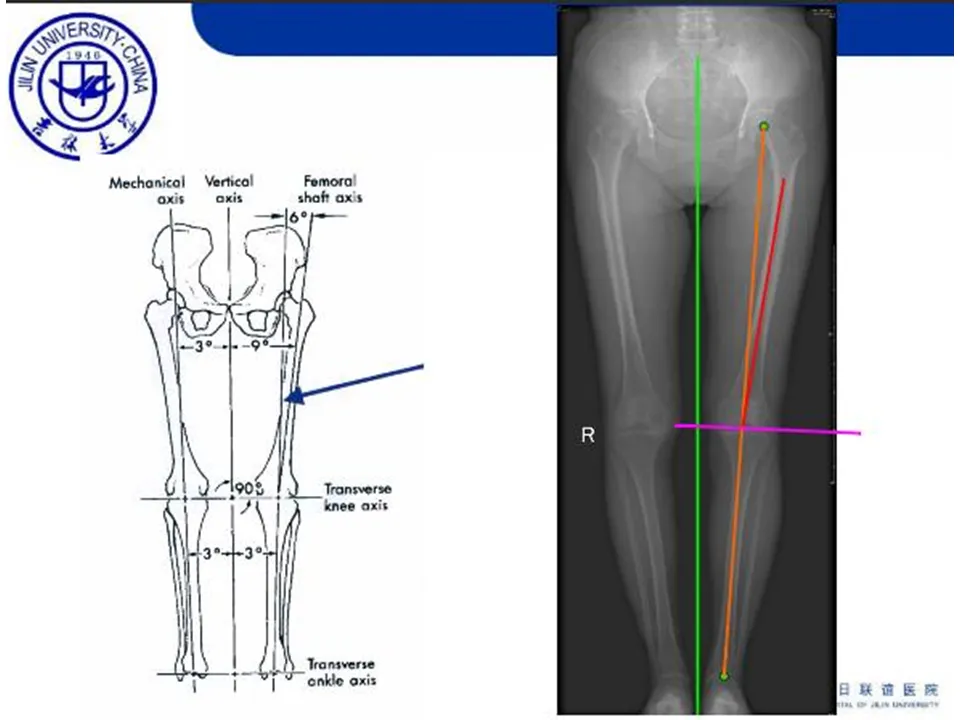

>【骨科PPT】全膝关节置换的截骨原则

【骨科PPT】全膝关节置换的截骨原则